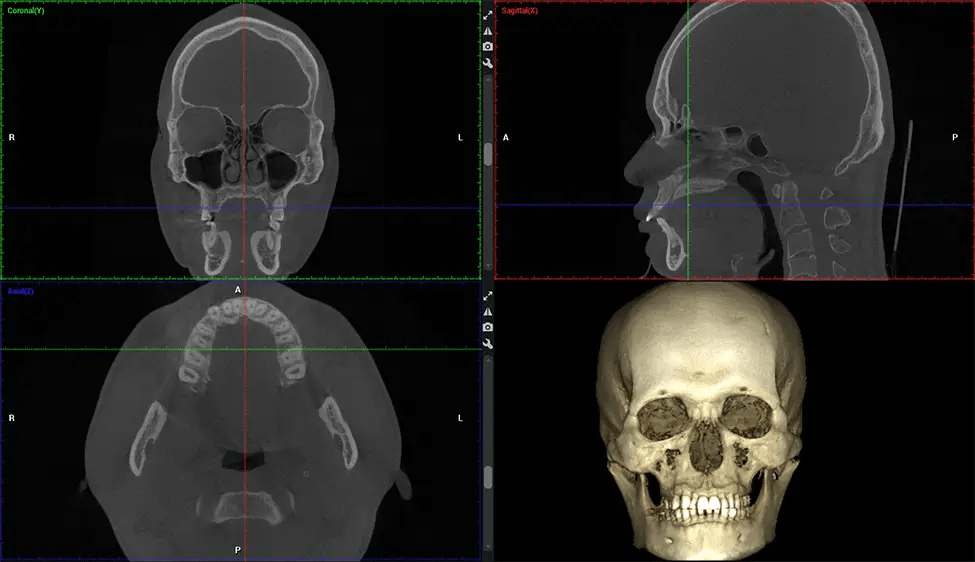

This 3D scan, called cone beam computed tomography, gives your dentist a more complete image of your oral anatomy and disease processes than a traditional X-ray. Unlike conventional X-rays, which capture a 2D image of your mouth from various angles, a 3D scan takes multiple digital X-rays for one image. It provides a complete view of your jaw, teeth, nerves, and soft tissues. This enhanced view allows dentists to detect minor issues not visible in traditional 2D scans, such as impacted wisdom teeth or bone fractures in the sinus cavity.

There are many benefits to using CBCT technology, especially compared to the traditional 2D X-ray format. One of the most significant advantages of CBCT scans is that they provide much more information than traditional X-rays. A scan lets your dentist see images from all angles of your jaw and mouth, including your sinuses, nasal cavity, cheekbones, and other surrounding areas. This added information helps your dentist craft a comprehensive treatment plan that addresses all aspects of your oral health.

The patient is first positioned in the CBCT scanner, which typically consists of a rotating arm that houses the X-ray source and a detector. The patient’s head is immobilized to ensure accurate image capture. The X-ray source and detector rotate around the patient’s head, capturing various X-ray images from multiple angles. As the X-ray source rotates, it emits the cone-shaped X-ray beam towards the detector. The detector captures the X-ray images, which are then processed by the CBCT software.

After the scanning process, the captured X-ray images are processed by the CBCT software, which applies algorithms to reconstruct a detailed 3D image of the scanned area. The software compiles these individual X-ray images and creates a digital 3D representation of the patient’s anatomy. The reconstructed 3D CBCT image can be viewed and analyzed by the dentist or radiologist. This image can be manipulated, rotated, and zoomed in or out to examine specific structures and evaluate the patient’s condition.

Planmeca Viso G7 CBCT ( Cone Beam CT Scan ) is designed to surpass the demands of industry leaders, specialists, and large institutions. It’s has a large ø25×30 cm sensor with four built-in cameras. It can capture unlimited volume sizes from a ø3×3 cm to a ø30x30cm volume capturing the skullcap through C7 on the cervical spine. The Planmeca Viso G7 offers the industry’s largest single volume scan of ø30×19 cm. It’s poised to handle advanced imaging modalities such as Planmeca ProFace® and Planmeca 4D™ Jaw Motion technology. The occipital head support allows an unimpeded view of facial tissue.